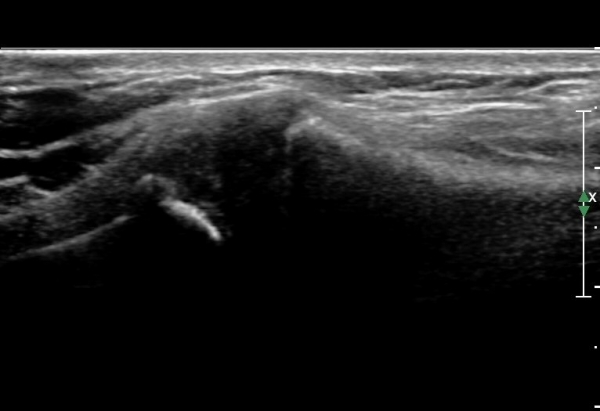

ÁÂÃø Èä°ñ¼â°ñ°üÀýÃÊÀ½ÆÄ°Ë»ç¿¡¼­ ƯÀÌ ¼Ò°ßÀ» º¸ÀÌÁö ¾ÊÀ½(»çÁø 1, 2).

out of plane ÃÊÀ½ÆÄÀ¯µµÇÏ °üÀý³» Áֻ翡¼­ °üÀý³»¿¡ ÁÖ»çħÀ» È®ÀÎÇϰí(»çÁø 6)